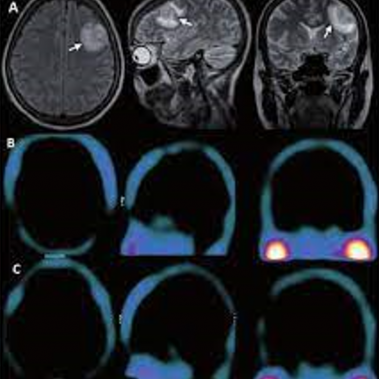

Cenedyt Servicio de Medicina Nuclear se creó hace más de 20 años. Las técnicas de imagen han tenido un desarrollo espectacular en los últimos años y cada vez juegan un papel más relevante en el proceso diagnóstico y terapéutico de los pacientes. El número de exploraciones realizadas es cada vez más elevado.

Estamos especializados en Medicina Nuclear y Densitometría. Nuestro objetivo y ofrecer al paciente la máxima calidad en Diagnóstico y tratamiento, basándonos en nuestra amplia experiencia y últimas tecnologías.